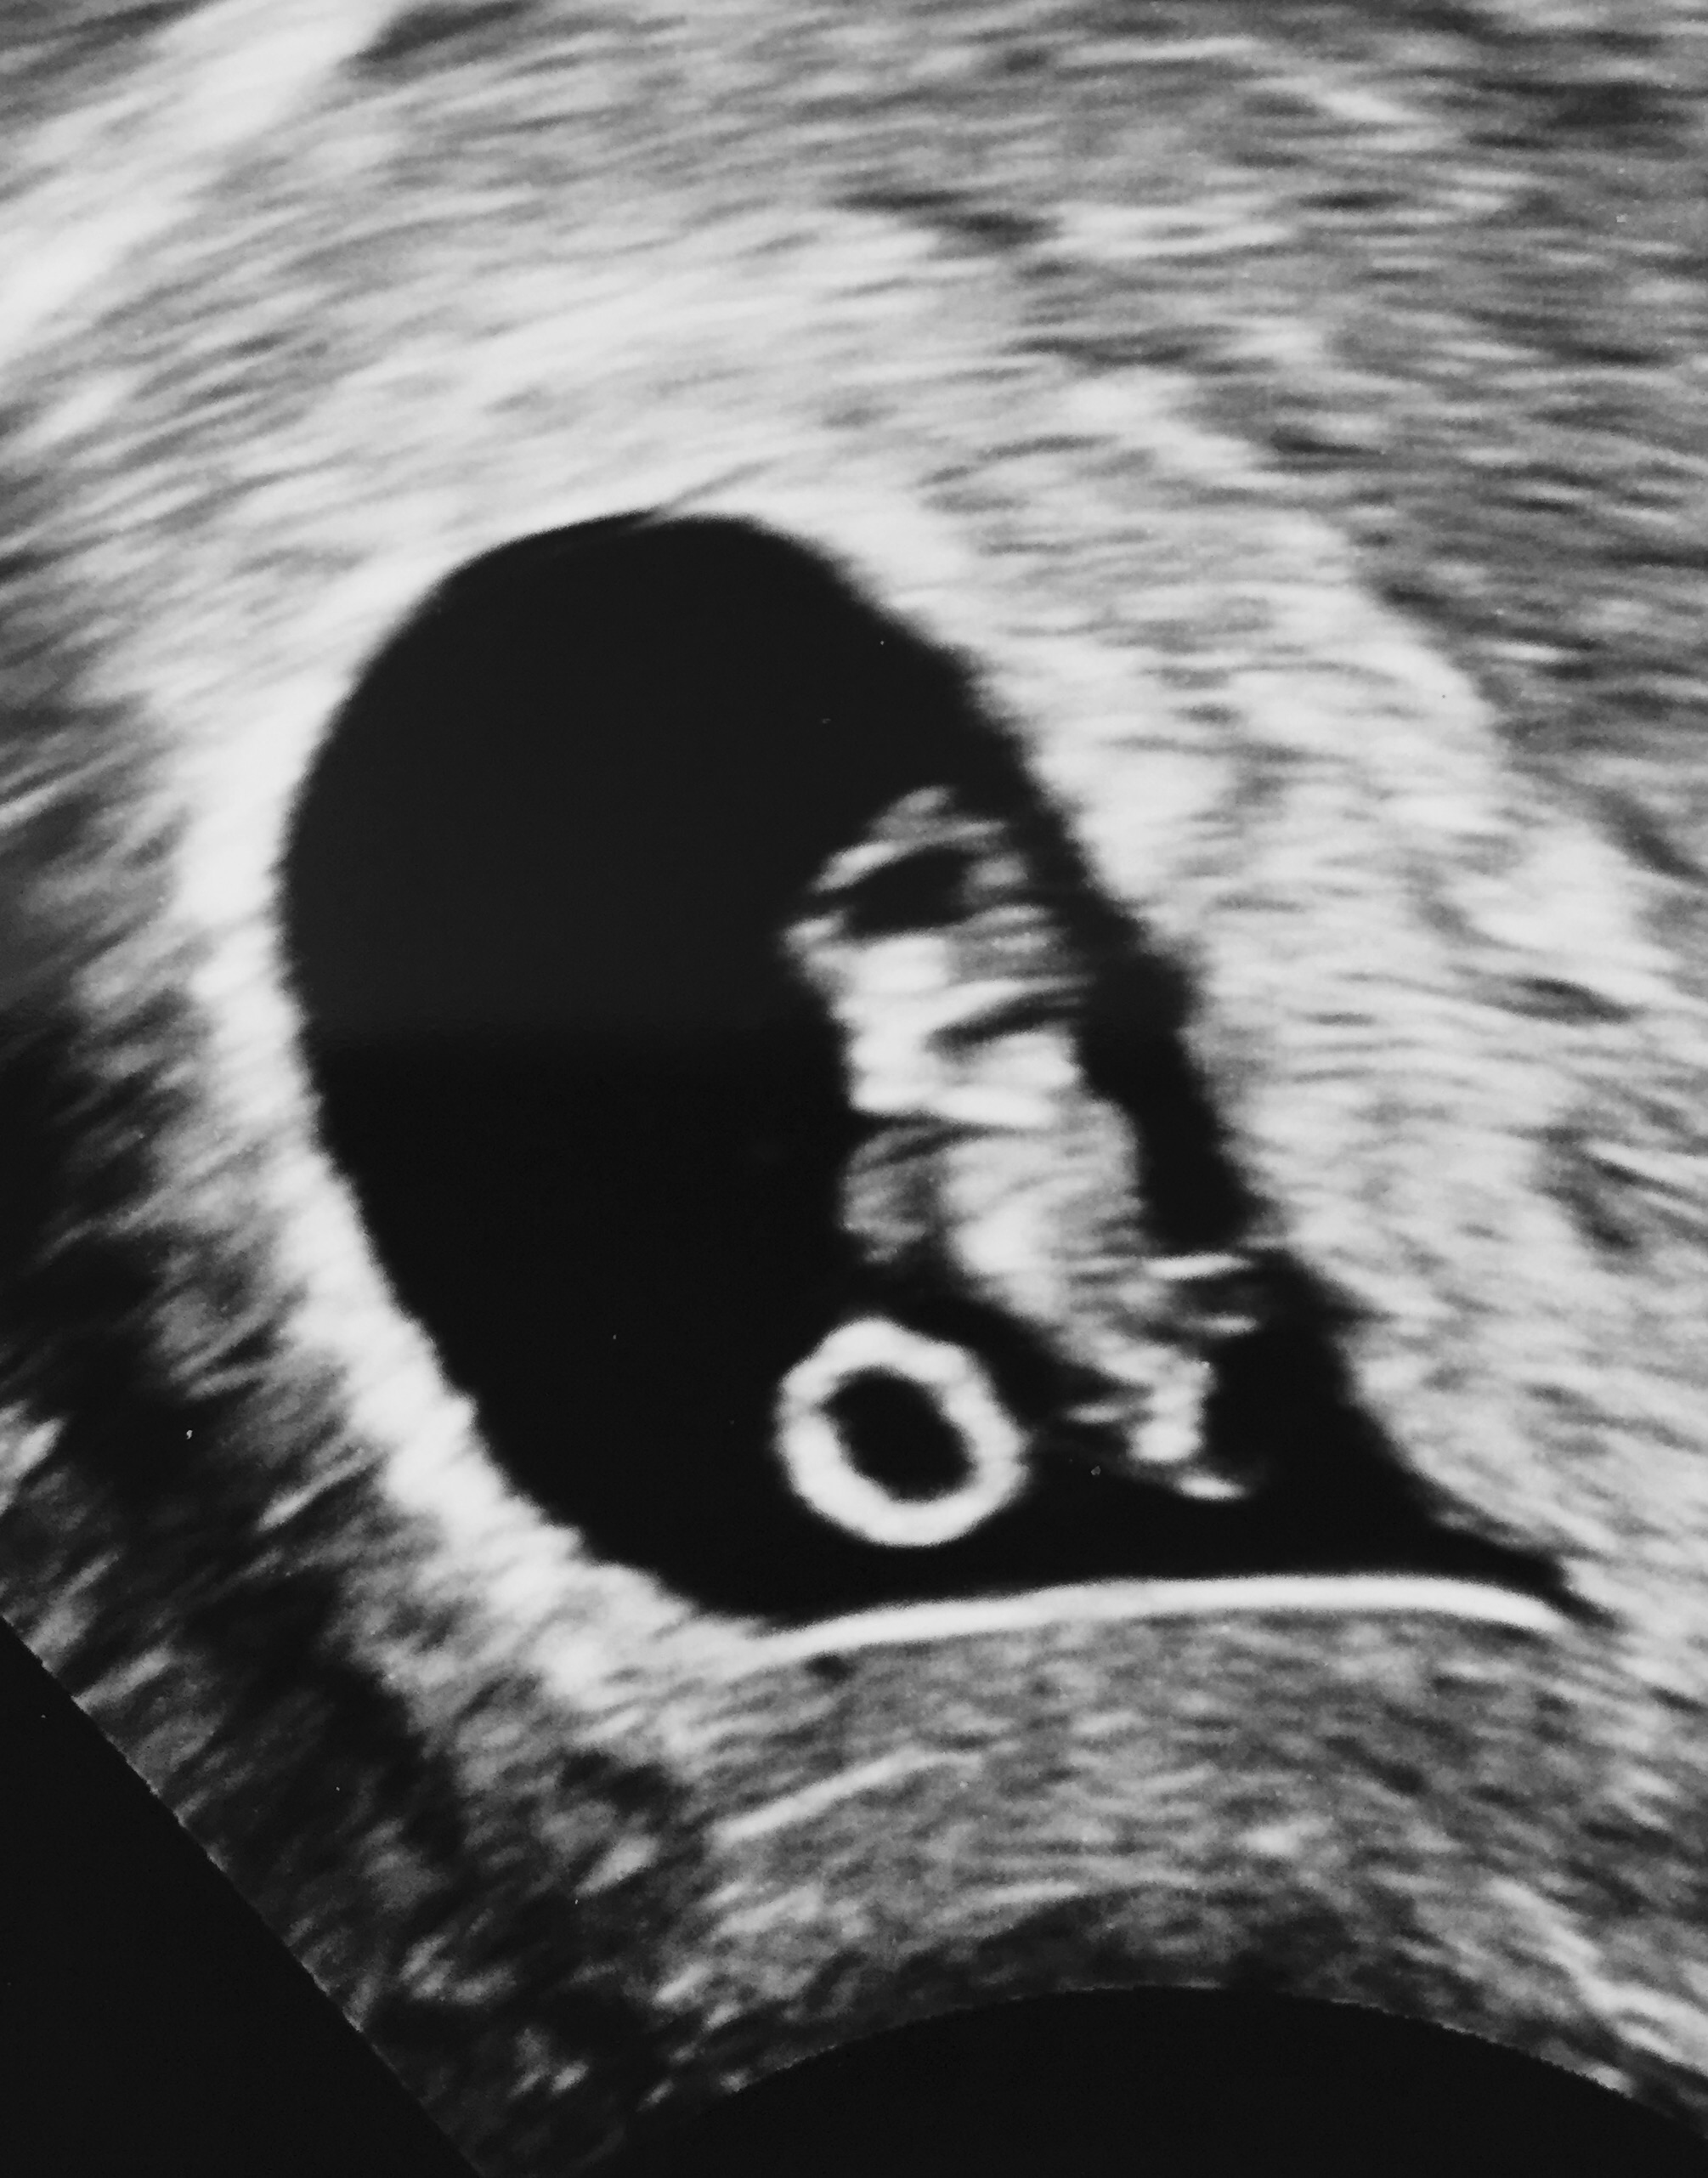

I had my first ultrasound on Wednesday when I was 9w6d. Baby was measuring at 10w3d. This picture isn't very clear because it's a picture of a picture.